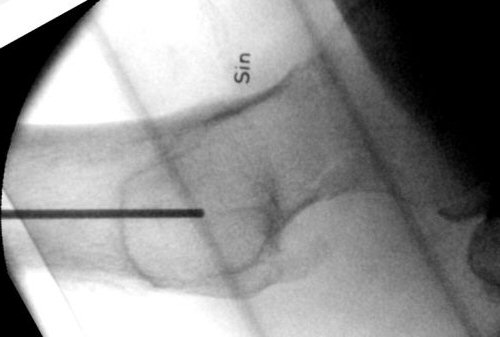

- Låt borret sitta kvar, använd distanshylsan, vinkla hylsan så det andra hålet i sidobild kommer nära dorsala kortex. Se till att komma nära kalkar, ha hög hastighet på borret och för in borret långsamt, annars är det risk att borret viker av när det ligger mot kalkar.

Genomlysning, läge för andra borrning. En k-tråd hålls över andra borret för att kontrollera placeringen.